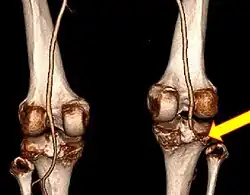

![]() | |

| Plain lateral X-ray of the left knee showing a posterior knee dislocation[1] | |